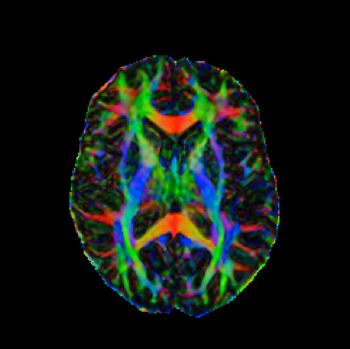

CHICAGO - Diffuse tensor imaging may help clinicians differentiate between mild traumatic brain injuries and post-traumatic stress disorder.